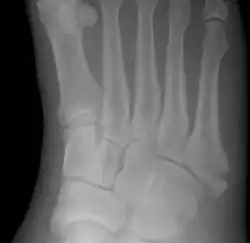

Jones fracture as seen on Xray

A Jones fracture is a broken bone in a specific part of the fifth metatarsal of the foot between the base and middle part .[8] In general, fifth metatarsal fractures heal readily, but a Jones fracture must be recognized and accurately diagnosed because of its higher rate of delayed healing or nonunion.[4] It results in pain near the midportion of the foot on the outside.[2] There may also be bruising and difficulty walking.[3] Onset is generally sudden.[4]

Diagnostic X-rays include anteroposterior, oblique, and lateral views and should be made with the foot in full flexion.

Other proximal fifth metatarsal fractures exist, although they are not as problematic as a Jones fracture. If the fracture enters the intermetatarsal joint, it is a Jones fracture. If, however, it enters the tarsometatarsal joint, then it is likely an avulsion fracture caused by pull from the fibularis brevis tendon. An avulsion fracture at the base of the fifth metatarsal is sometimes called a "dancer's fracture" or a "pseudo Jones fracture", and usually responds readily to non-operative treatment.[18] The X-ray appearance of the developmental "apophysis" in this area may have some resemblance of a fracture, but is not a fracture; it is the secondary ossification center of the metatarsal bone. It is a normal finding that occurs at this site in adolescents.[19] If an injury to that area has occurred, the physician is often able to interpret certain radiographic clues to make the differentiation. An avulsion fracture at this location is typically extra-articular and oriented transversally as compared to the longitudinal orientation of an unfused apophysis.[19]